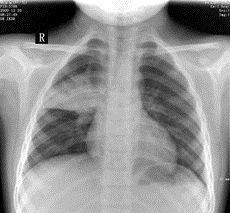

肺炎鏈球菌肺炎2.胸部體徵:早期只有輕度叩診濁音或呼吸音減弱。病程第2~3日肺實變後有典型叩診濁音、語顫增強及管性呼吸音等。消散期可聽到濕羅音。少數病例始終不見胸部異常體徵。確診須靠X線檢查。

3.X線檢查:早期可見肺紋理加深或限局於一個節段的淺薄陰影,以後有大片陰影均勻而緻密,占全肺葉或一個節段(圖24-8),經治療後逐漸消散。可見肺大泡。少數病例出現胸腔積液。值得指出,在肺部體徵出現之前,即可能用X線透視查出實變。多數患兒在起病3~4周后X線陰影消失。